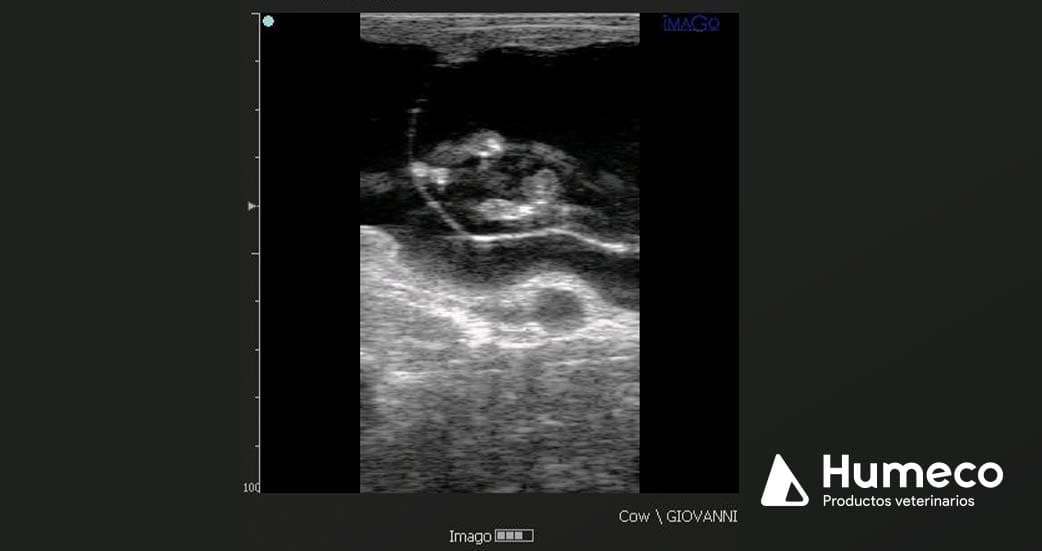

La prueba se llevó a cabo en vacas gestantes entre los días 55 y 110 de gestación, con un equipo de ultrasonido ultra portátil, IMAGO (ECM France), y con una sonda lineal de 5,0-7,5 MHz.